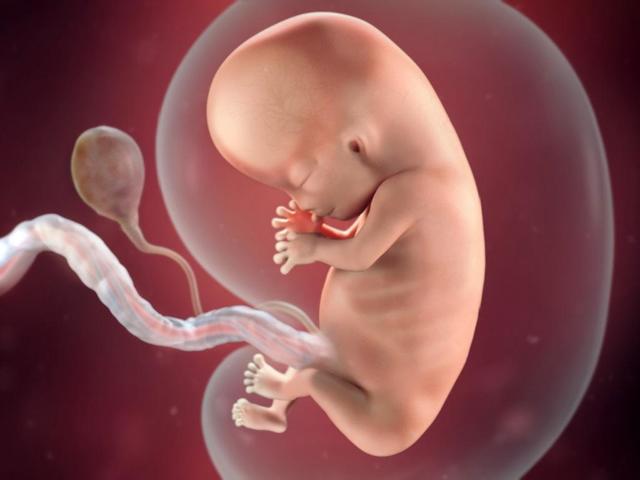

Week 2

In week two, ovulation occurs and the sperm is then able to fertilize the egg in the fallopian tube. The fertilized egg then starts to divide and head down towards the uterus.

• Week 3

Week 3

In week three the fertilized egg continues to divide and head toward the uterus. Also the gender and features of the baby are determined when the egg is fertilized.